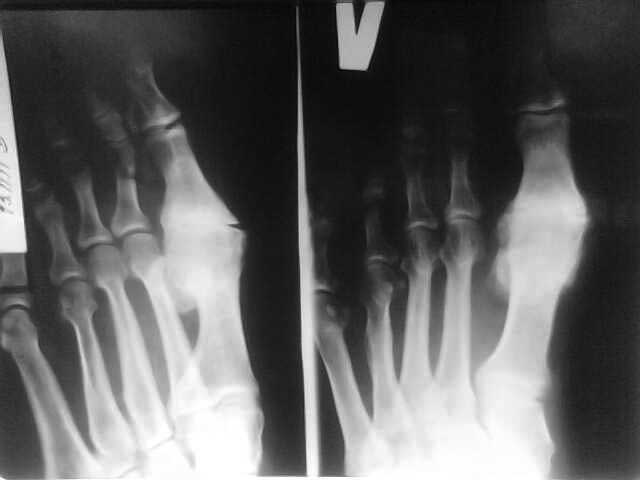

Уважаемые коллеги! Доброго времени суток. Мужчина, возраст 40 лет. Работает на себя(строитель). По характеру профессиональной деятельности часто ронял себе на ногу тяжелые предметы (радиаторы отопления, мешки с сухими смесями и т.д.)

За помощью никогда не обращался. В настоящий момент беспокоят боли в области 1 плюсне-фалангового сустава, нарушающие походку, периодические щелчки в этой области. Объективно: область 1 ПФС увеличена в объеме за счет костных разрастаний, признаков воспаления нет, омозолелая кожа на внутренней поверхности, движения в суставе качательные, б/болезненные. Хочет избавится от боли и щелчков, как можно быстрей. Извините за качество снимка- сфотографировано телефоном.